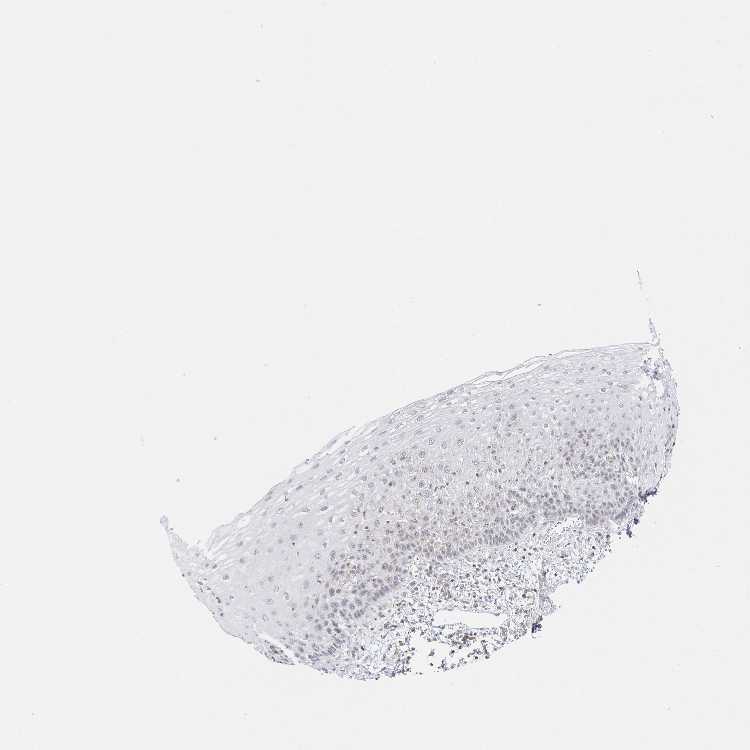

ESOPHAGUS - Antibody stainingi

Antibody staining in the annotated cell types in the current human tissue is reported as not detected, low, medium, or high, based on conventional immunohistochemistry profiling in selected tissues. This score is based on the combination of the staining intensity and fraction of stained cells.

Each image is clickable and will lead to virtual microscopy that enables deeper exploration of all samples and also displays staining intensity scores, fraction scores and subcellular localization as well as patient and tissue information for each sample.

Antibody HPA060744Antibody HPA060960

Squamous epithelial cells LowLow